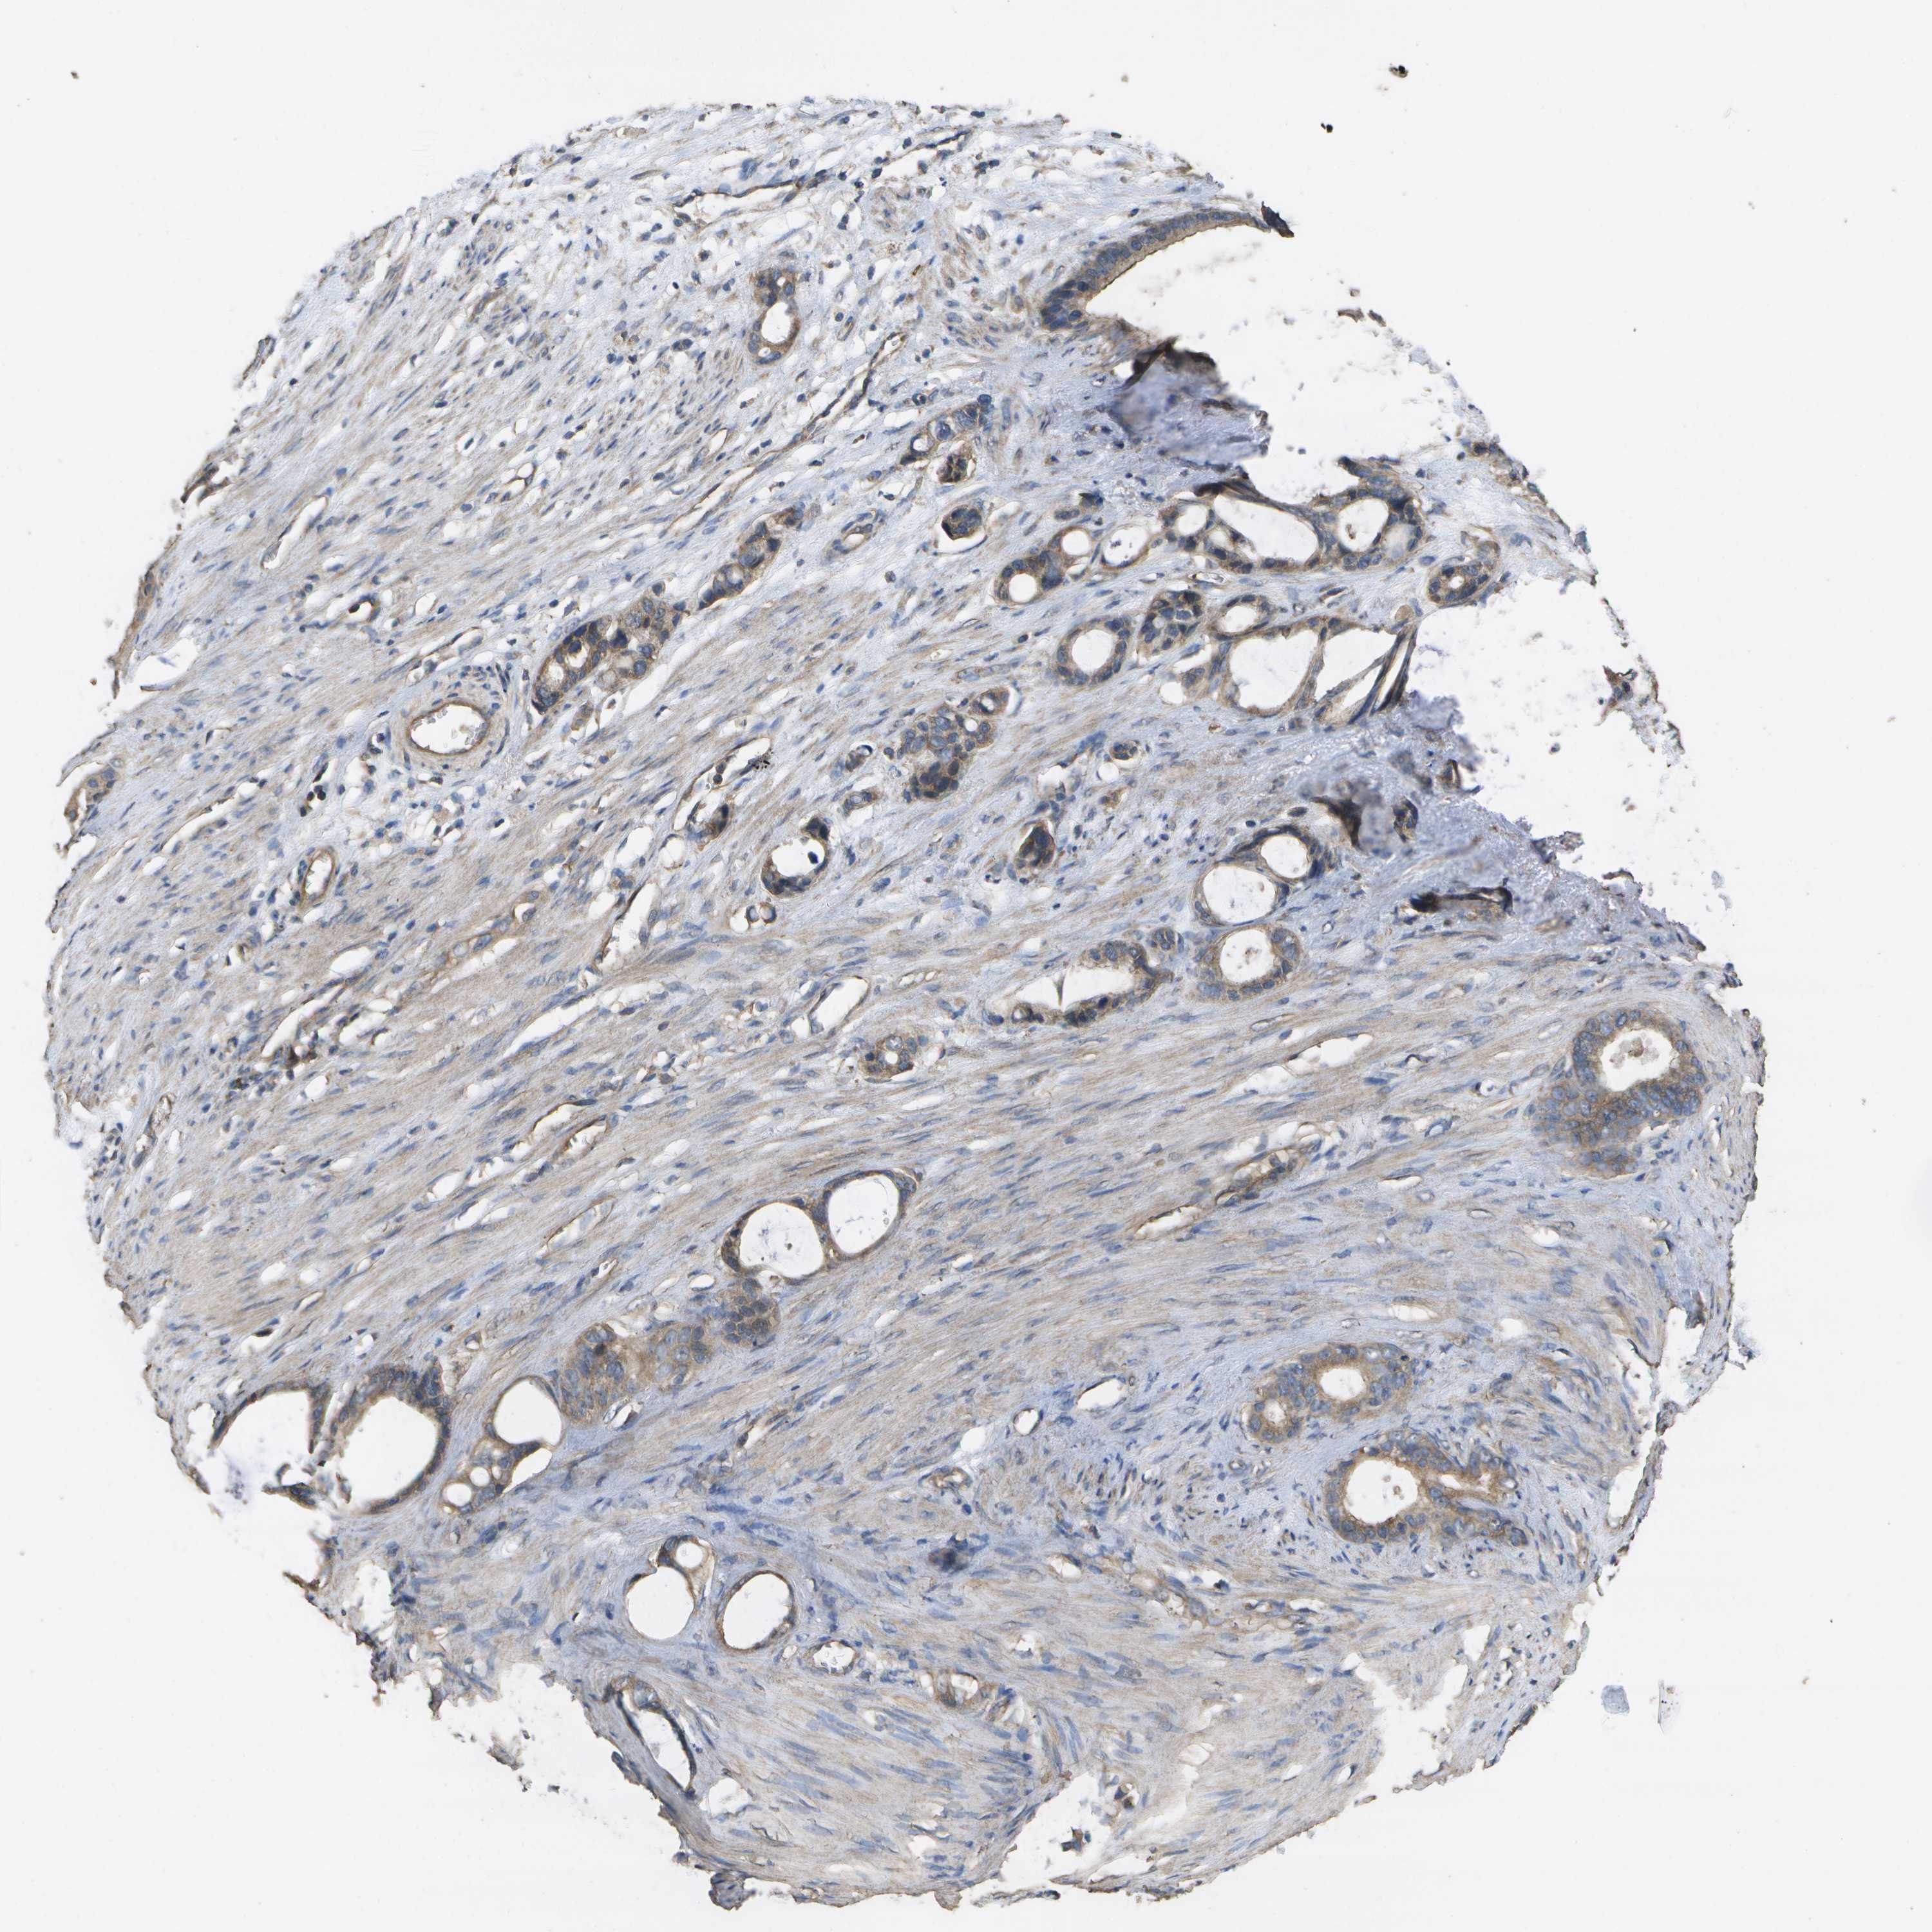

STOMACH CANCER - Protein expressioni

A mouse-over function shows sample information and annotation data. Click on an image to view it in a full screen mode. Samples can be filtered based on level of antibody staining by selecting one or several of the following categories: high, medium, low and not detected. The assay and annotation is described here.

Note that samples used for immunohistochemistry by the Human Protein Atlas do not correspond to samples in the TCGA dataset.

Antibody stainingi

Antibody staining in the annotated cell types in the current human tissue is reported as not detected, low, medium, or high, based on conventional immunohistochemistry profiling in selected tissues. This score is based on the combination of the staining intensity and fraction of stained cells.

Each image is clickable and will lead to virtual microscopy that enables deeper exploration of all samples and also displays staining intensity scores, fraction scores and subcellular localization as well as patient and tissue information for each sample.

Antibody CAB017714

Staining

High

Medium

Low

Not detected

Intensity

Strong

Moderate

Weak

Negative

Quantity

>75%

75%-25%

<25%

None

Location

Nuclear

Cytoplasmic/membranous

Cytoplasmic/membranous,nuclear

Adenocarcinoma, NOS

Adenocarcinoma, High grade